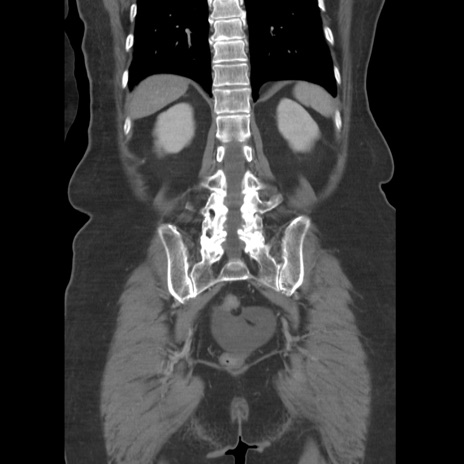

症例19(冠状断像)

【症例】80歳代女性

【主訴】下腹部痛

【現病歴】約8時間前より下腹部痛の出現あり、救急外来受診。

【既往歴】両側付属器切除

【身体所見】意識清明、下腹部正中に手術痕あり、その部位に一致して圧痛と反跳痛あり。腸蠕動音は亢進。

【データ】WBC 9300、CRP 0.15